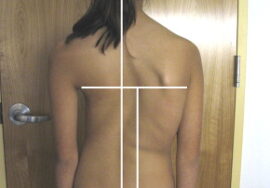

يُعد اعوجاج العمود الفقري مجهول السبب عند المراهقين (Adolescent Idiopathic Scoliosis – AIS) من أكثر اضطرابات العمود الفقري شيوعًا في مرحلة النمو، ويُعتبر العلاج بحزام اعوجاج العمود الفقري (Brace) الطريقة التحفظية الأكثر استخدامًا لتصحيح الانحناء ومنع تفاقمه.

إذا لاحظتِ علامات انحناء في ظهر طفلك، أو لاحظتِ عدم تماثل بين الجانبين، فلا تتردد الأن في استشارة مجانيه من طبيب متخصص.

إذا لاحظتِ علامات انحناء في ظهر طفلك، أو لاحظتِ عدم تماثل بين الجانبين، فلا تتردد الأن في استشارة مجانيه من طبيب متخصص.

إذا لاحظتِ علامات انحناء في ظهر طفلك، أو لاحظتِ عدم تماثل بين الجانبين، فلا تتردد الأن في استشارة مجانيه من طبيب متخصص.